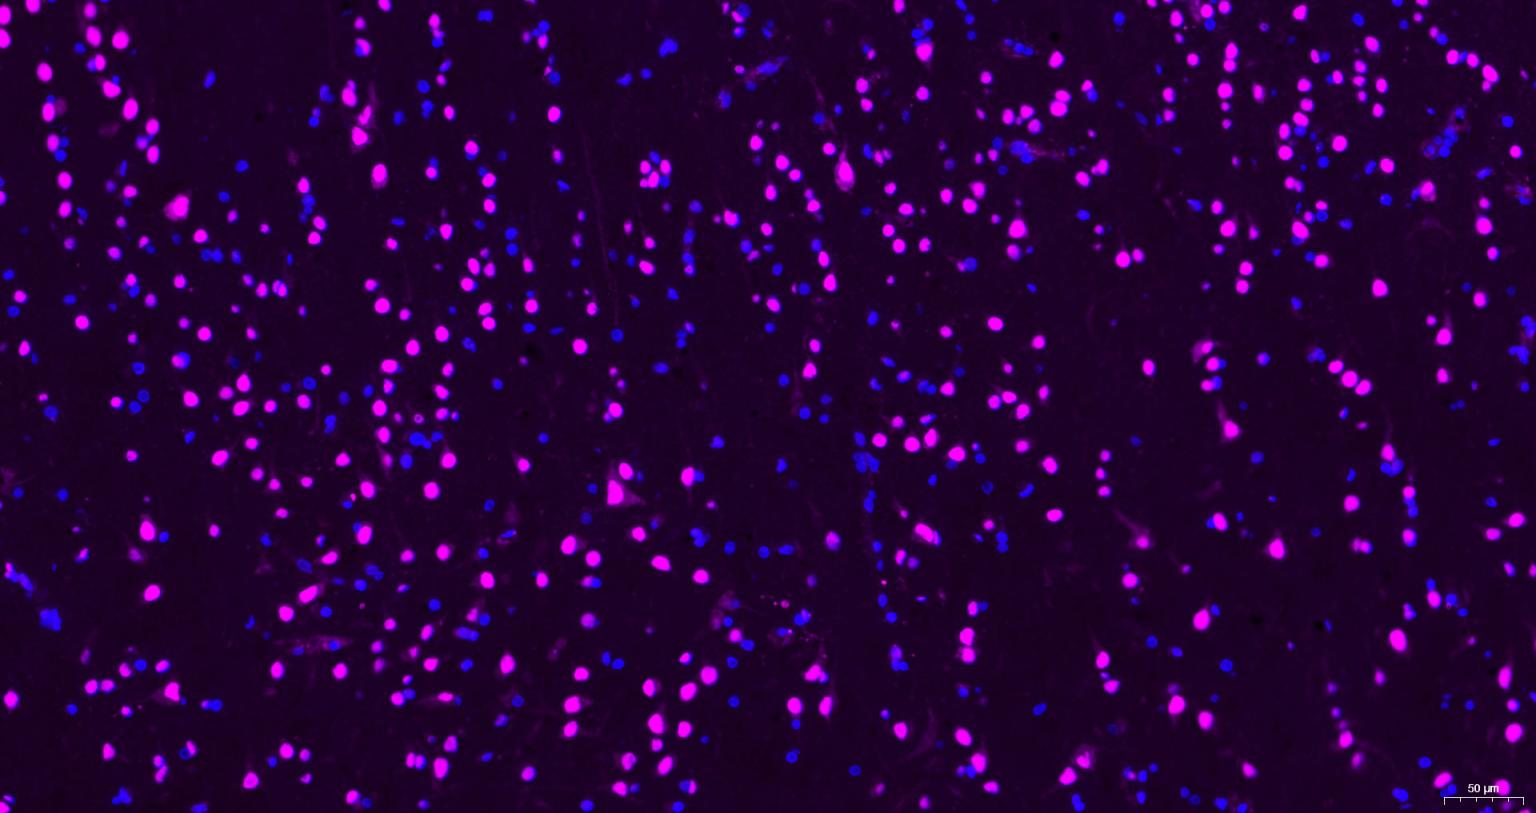

Paraformaldehyde-fixed, paraffin embedded Mouse brain; Antigen retrieval by boiling in sodium citrate buffer (pH6.0) for 15 min; Antibody incubation with AKT1 Monoclonal Antibody, Unconjugated(bsm-52010R) at 1:200 overnight at 4°C, followed by a Cy5 conjugated Goat Anti-Rabbit IgG (bs-0295G-Cy5)antibody at 37°C for 90 minutes, DAPI (blue, C02-04002) was used to stain the cell nuclei.